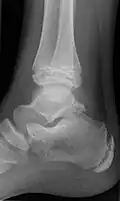

Wrist and hand

| Accessory bone | Prevalence on the right (R) and left (L)[5] |

|---|---|

| Os ulnostyloideum | 1.5% R, 2.4% L |

| Os centrale | 1.3% R, 2.1% L |

| Os trapezium secundarium | 0.5% R, 2.1% L |

| Os styloideum | 1.2% R, 1.2% L |

| Os radiale externum | 1% R, 0.9% L |

| Os triangulare | 1% R, 0.9% L |

| Os paratrapezium | 0.3% R, 0.9% L |

| Os capitatum secundarium | 0.8% R, 0.3% L |

| Os Hypotriquetrum | 0.5% R |

| Os hypolunatum | 0.3% L |

| Os epilunatum | 0.3% R, 0.3% L |

| Os ulnare externum | 0.3% L |

| Os pisiforme secundarium | 0.3% R |

| Os epitrapezium | 0.3% L |

| Os vesalianum manus | 0.3% L |

Os ulnostyloideum

The os ulnostyloideum is an ulnar styloid process that is not fused to the rest of the ulna bone.[6] On X-rays, an os ulnostyloideum is sometimes mistaken for an avulsion fracture of the styloid process. However, the distinction between these is extremely difficult.[6][7] It is alleged that the os ulnostyloideum has a close relationship with or is synonymous with the os triquetrum secundarium.[8]

Os centrale

The os carpi centrale (also briefly os centrale) is, where present, located on the dorsal side of the wrist between the scaphoid, the trapezoid and capitate, radially to the deep fossa of the capitate. The bone is present in almost every human embryo of 17–49 mm length, but then usually fuses with the ulnar side of the scaphoid. Sometimes it fuses with the capitate or the trapezoid. The literature also refers to an os centrale at the palm of the carpus, but this existence is questioned.[6]

In most primates, including orangutans and gibbons, the os centrale is an independent bone that is attached to the scaphoid by strong ligaments. Conversely, in African apes and humans, the os centrale normally fuses to the scaphoid early in development.[9] In chimpanzees, the bone fuses with the scaphoid first after birth, while in gibbons and orangutans this occurs first at older age.[10] A good number of scholars have construed the scaphoid-centrale fusion as a functional adaptation to knuckle-walking,[11] since a fused morphology would better cope with the increased shear stress on this joint during this kind of quadrupedal locomotion. The results from a simulation study have shown that fused scaphoid-centrales show lower stress values as compared to non fused morphologies, thus supporting a biomechanical explanation for the scaphoid-centrale fusion as a functional adaptation for knuckle-walking.[12]